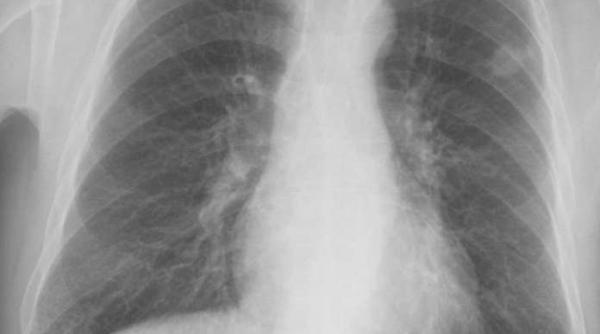

În fiecare oră, un român este diagnosticat cu o formă de cancer pulmonar. Ce trebuie să știi despre diagnosticul precoce și tratament